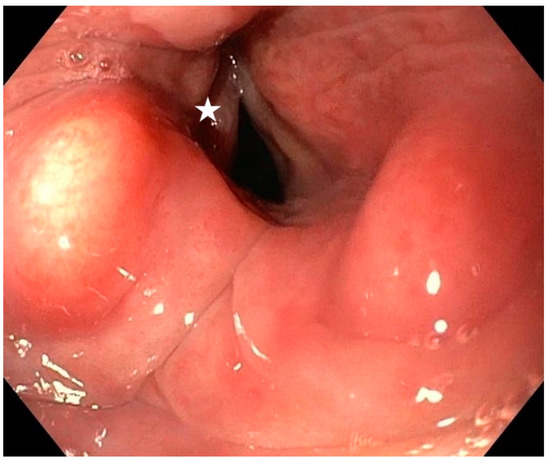

3.1. Analysis of the Qualitative Data Obtained during Ultrasound and MRI in Patients with Goiter Compared to Direct Laryngoscopy